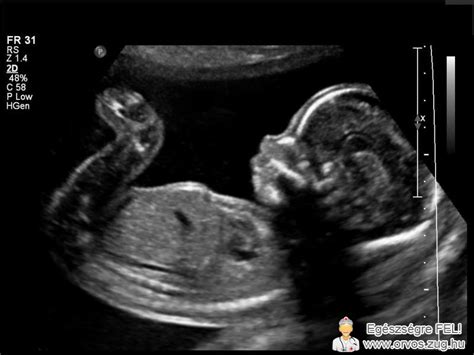

A petefészkeket különösen hüvelyi ultrahang vizsgálattal lehet jól látni, mert ilyenkor a szeméremcsont nem árnyékolja le a kritikus területeket. A színkódolt hüvelyi ultrahang vizsgálat segítségével a ciszta rosszindulatúsága is kizárható vagy megerősíthető.

A sejtes ciszta (granulóza sejtes ciszták) nagy valószínűséggel féloldaliak, azaz vagy csak a bal, vagy csak a jobb petefészekben képződnek. Nem nagy a méretük és leggyakrabban koraterhességben találkozhatunk velük, esetlegesen az UH-on látszódhatnak. Nincs vele semmilyen teendőnk, a sárgatest a terhesség legkésőbb 10. hetéig működik.